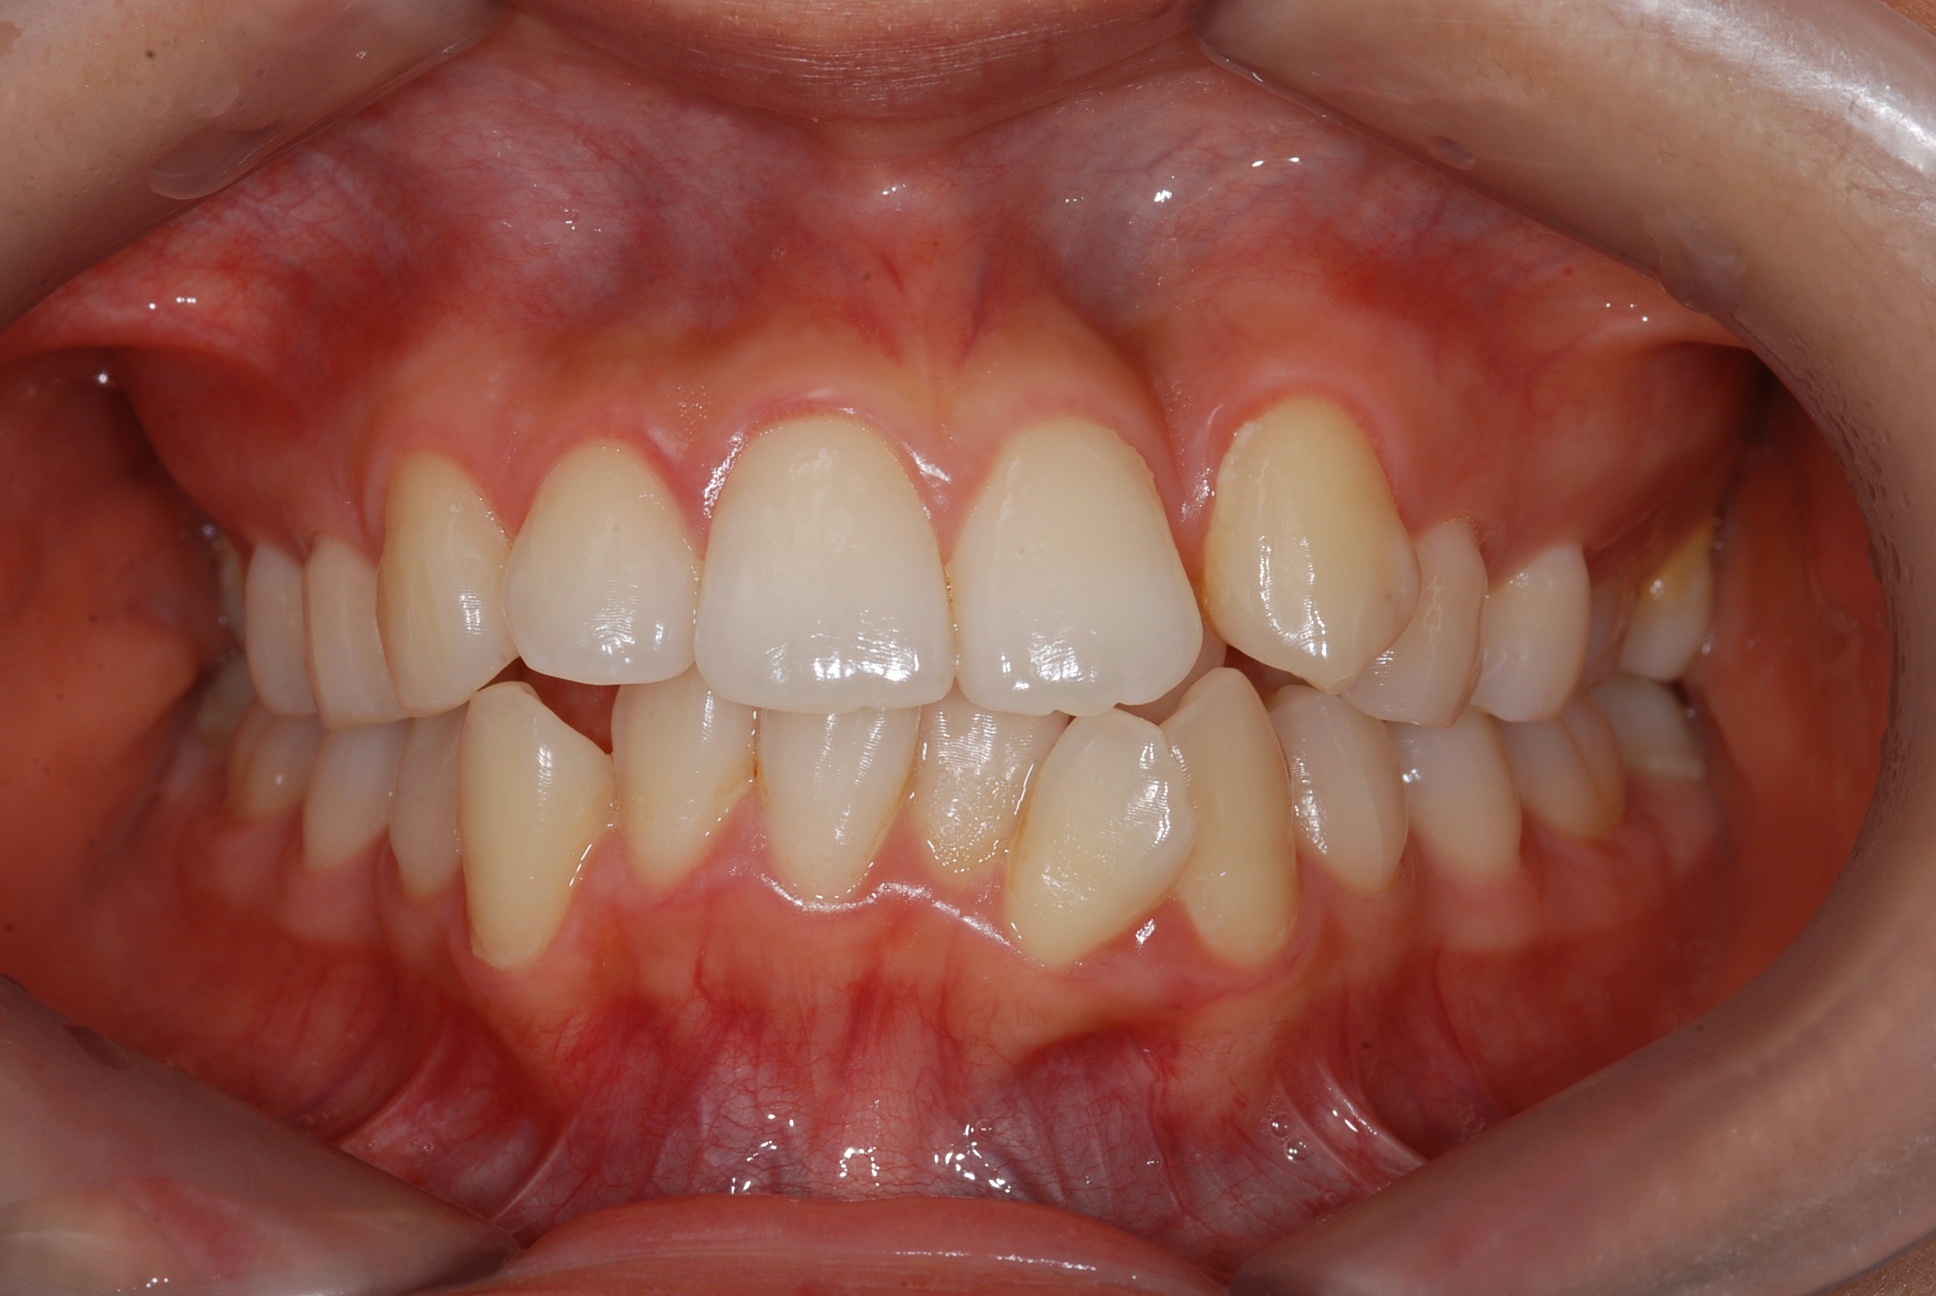

치료 전 사진입니다.